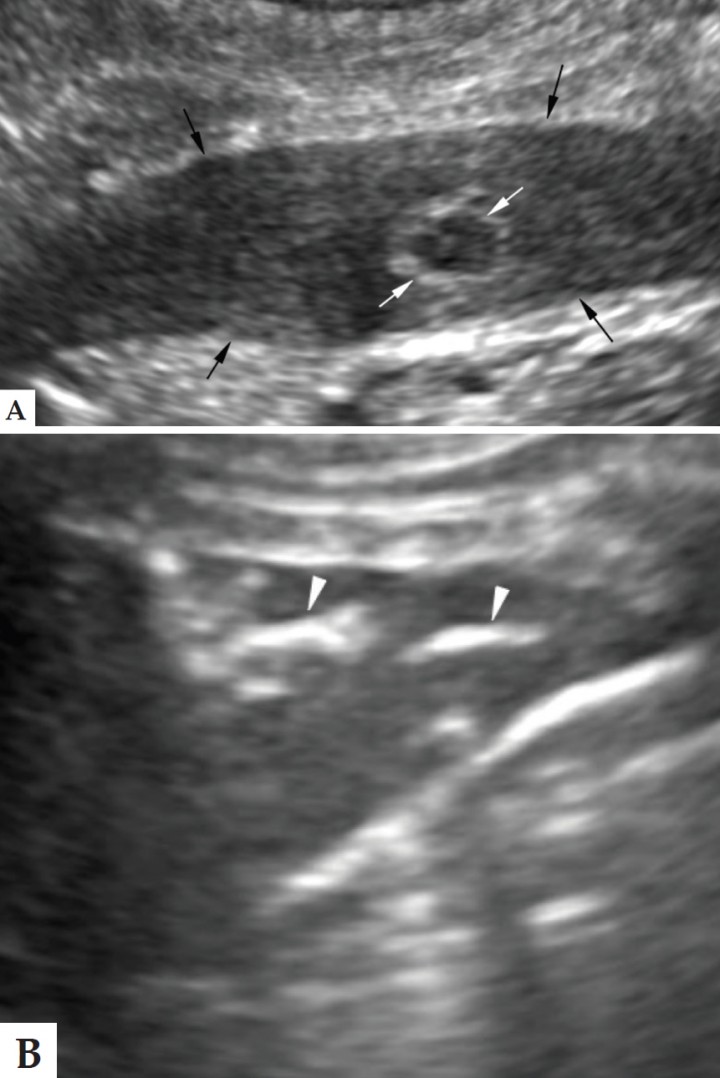

En este caso se realizó una ecografía torácica, observándose consolidación del lóbulo pulmonar craneal izquierdo, parénquima de aspecto hepatizado y estructuras tubulares dilatadas rellenas de líquido en la zona craneal, y broncogramas aéreos en la zona caudal (Fig. 3). El estudio Doppler reveló ausencia de flujo. Los nódulos linfáticos mediastínicos estaban moderadamente aumentados de tamaño (1 cm). Estos hallazgos sugieren consolidación asociada a torsión pulmonar, proceso inflamatorio o neoplasia de infiltración difusa.

<p>Imágenes ecográficas del lóbulo pulmonar craneal izquierdo consolidado (flechas negras) con un broncograma líquido señalado por la flecha blanca (A) y con broncogramas aéreos señalados por las puntas de flecha blancas (B).</p>

Imágenes ecográficas del lóbulo pulmonar craneal izquierdo consolidado (flechas negras) con un broncograma líquido señalado por la flecha blanca (A) y con broncogramas aéreos señalados por las puntas de flecha blancas (B).

La ecografía permite detectar efusión pleural y consolidación pulmonar con broncogramas líquidos. Con frecuencia se observan focos de gas hiperecogénicos dispersos en la zona central del lóbulo torsionado, y que representan enfisema vesicular. El examen con Doppler permite detectar la ausencia de flujo venoso y la reducción del flujo arterial en el lóbulo afectado. Aunque la ecografía en estos pacientes es útil, generalmente no permite diferenciar una consolidación por torsión de la producida por neumonía o neoplasia pulmonar infiltrativa.[ D’Anjou MA, Tidwell AS, Hecht S. Radiographic diagnosis of lung lobe torsion. Vet Radiol Ultrasound 2005; 46:478-484. [PubMed] ]